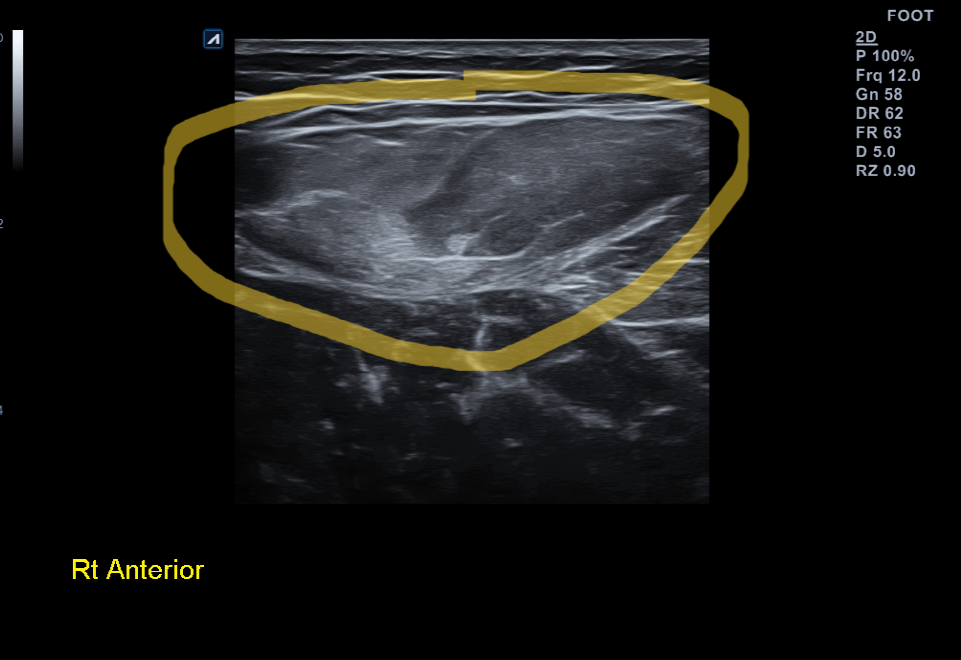

x-ray 검사 상에서는 특별한게 없습니다. 초음파 검사상에서는 근육내 출혈에 의해 양쪽 대퇴직근이 하얗게 (hyperechoic)하게 보이고 있었습니다.